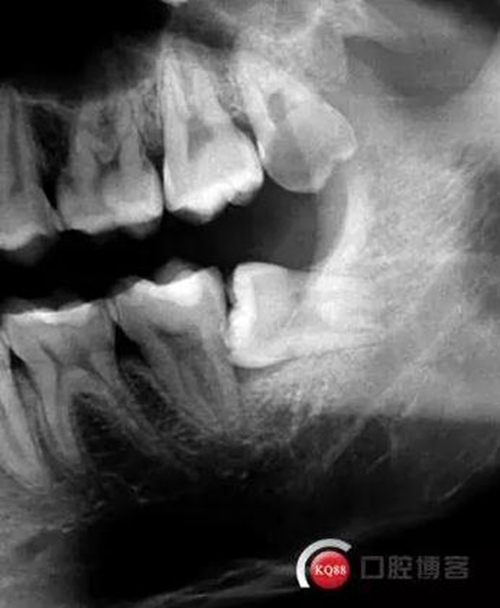

檢查:口內(nèi)可見38未完全萌出,無松動,周圍牙齦顏色正常,叩診(—)觸診(—),X線顯示近中阻生,雙根

處理:治療計(jì)劃及費(fèi)用已說明,知情同意后,排除拔牙禁忌癥:口腔黏膜消毒,左下頜阻滯麻醉成功后,切開翻瓣,渦輪機(jī)去除近中阻力,向近中挺出患牙,拼對牙體完整,清創(chuàng),置明膠海綿,縫合傷口,咬棉球壓迫止血